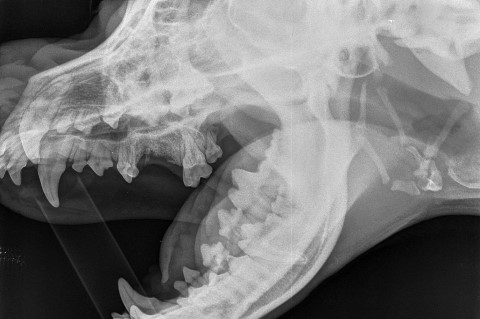

Dentalröntgen

Um Wurzelläsionen, Kiefervereiterungen und die Vitalität einzelner Zähne beurteilen zu können, ist es manchmal nötig, mit hochauflösenden Zahnfolien strahlungsarme Röntgenaufnahmen der zu beurteilenden Kieferbereiche zu machen. So können gesund wirkende, aber wurzelkranke Zähne identifiziert und behandelt werden. Aber auch überflüssige Zahnextraktionen bei Schmelzdefekten oder Verfärbungen ohne Wurzelschaden können vermieden werden.